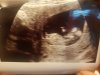

Więc ja już po wizycie

Według OM termin 9.01

Według USG termin 10.01

CRL 4.3 cm

BPD 1.3 cm

Przeciętność karku 1.1

Kość nosa uwidoczniona

Ruchy płodu obecne

Płyn owodniowy prawidłowy

Serduszko 160/ min

Łożyska tylna ściana

Załączniki

• 20200622_155409.jpg

20200622_155409.jpg

1,3 MB · Wyświetleń: 103